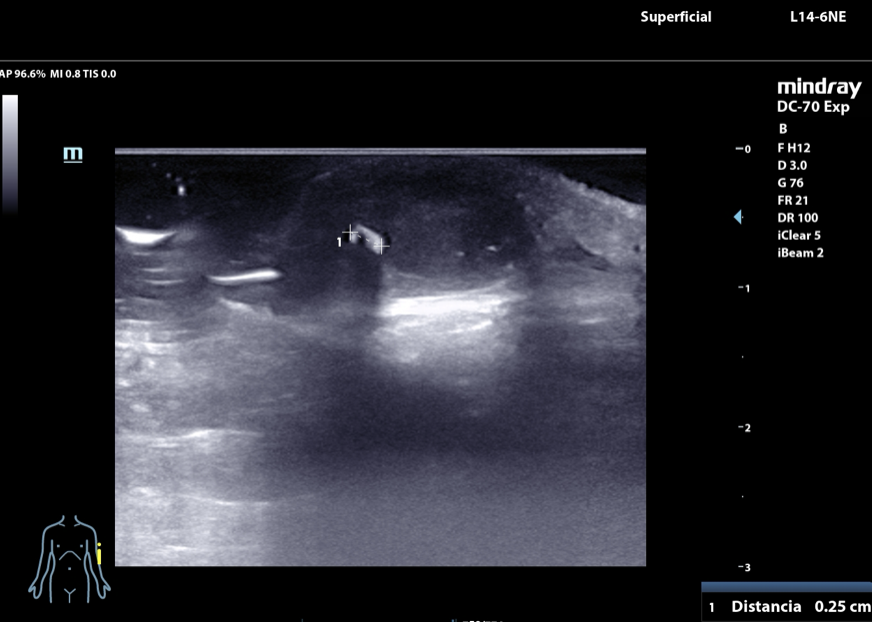

Hombre de 17 años que acude a consulta en agosto de 2024 por dolor y tumefacción a nivel de epicóndilo de codo izquierdo. En abril sufrió una caída contra una palmera y desde ese momento ha consultado hasta en tres ocasiones en Urgencias por dolor. En el informe de urgencias se diagnostica un absceso cutáneo de 1 cm de diámetro y se solicita una radiografía de codo (sin alteraciones). Se alta con antibioterapia. En consulta persiste la sintomatología. Se revisa la radiografía y se repite la exploracion física: tumefacción de 1,5 cm de diámetro en epicóndilo izquierdo. Se decide realizar una ecografía músculoesquelética con identificación de un cuerpo extraño tras lo que se procede a su extracción que resulta ser una púa de 2,6 cm.

Tras la ecografía se procede a la extracción de dicho cuerpo extraño que resulta ser una púa de palmera de 2,6 cm de longitud.